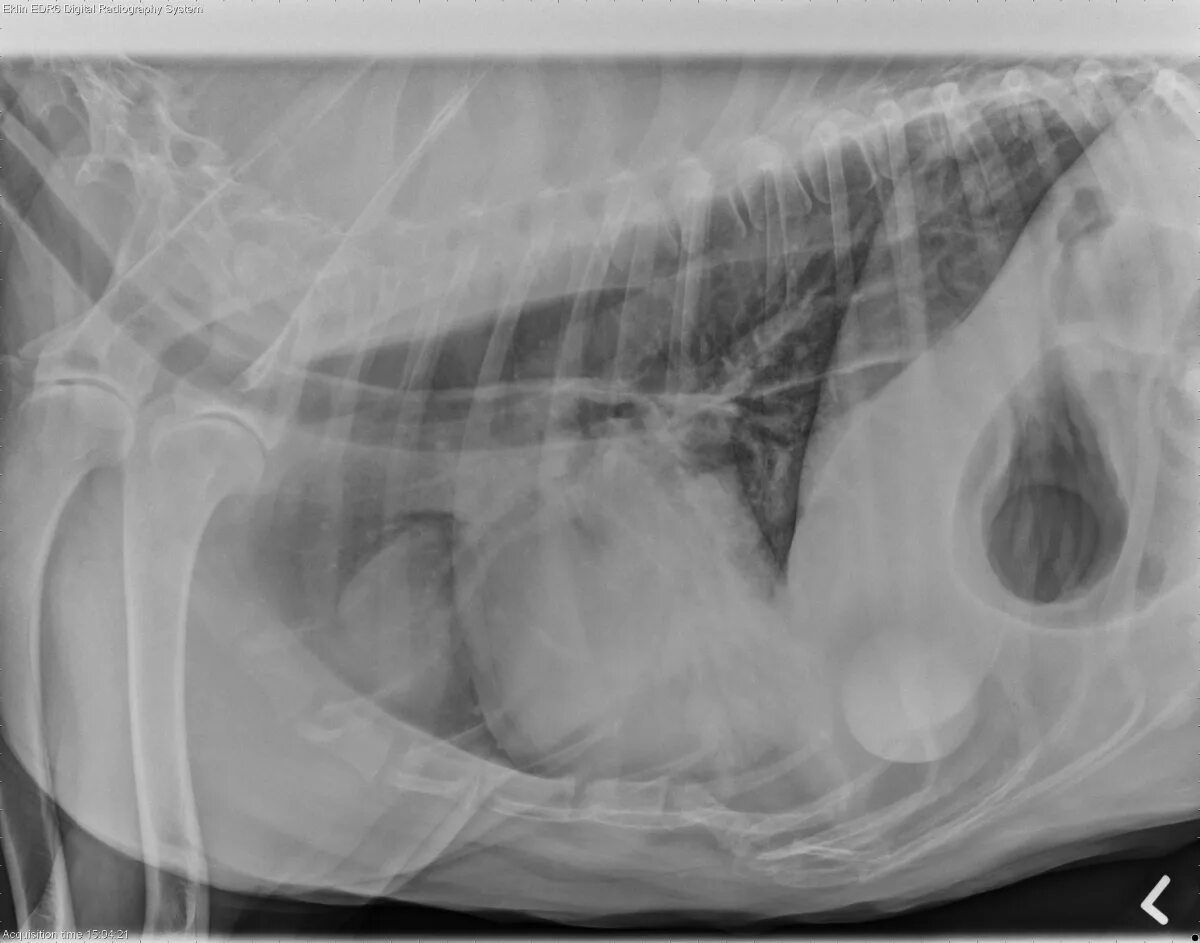

Лимфома у собак симптомы